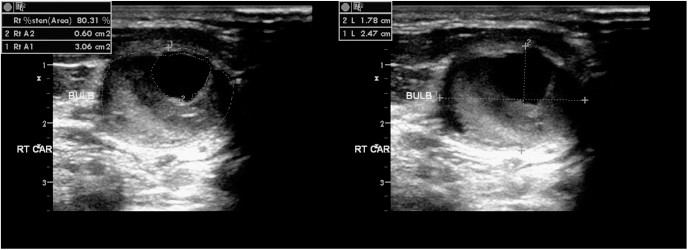

죽상경화 플라크 성상 평가

플라크는 저에코(연성), 등·고에코(섬유·석회화), 표면 불규칙·궤양 등으로 묘사됩니다. 영상에서 연성·불안정 소견은 색전 위험과 연관될 수 있어 주의 깊은 추적과 치료 최적화가 권장됩니다.

- Plaque morphology: 저에코/고에코, 불규칙, 궤양 등 성상 기술.

- 진단 문구 예시: ‘우측 ICA 근위부 중등도 협착 의심’, ‘양측 CCA 분지부 석회화 플라크’, ‘좌측 IMT 증가’.